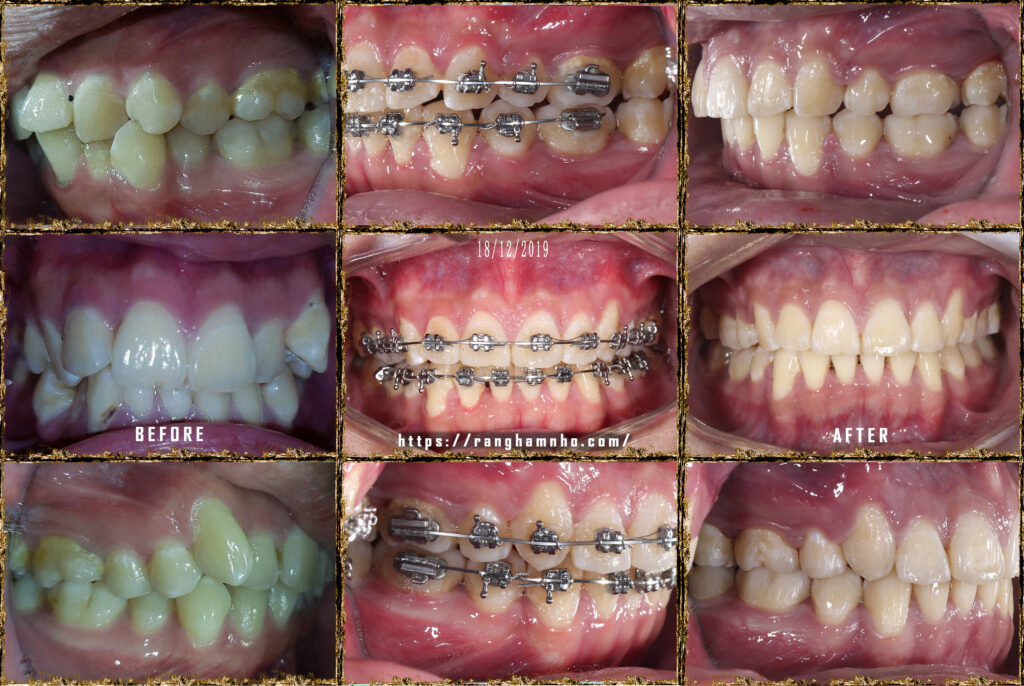

Bệnh nhân nam sinh năm 1998. Khớp cắn hạng I, với chen chúc và khấp khểnh nặng ở cả 2 hàm trên và dưới.

Cung hàm trên và cung hàm dưới đều hẹp, răng thiếu chỗ nghiệm trong.

Kế hoạch: Nhổ 4R4, chỉnh nha phân đoạn

Làm phẳng mặt phẳng cắn bằng cung tiện ích TMA 17×25 hai hàm